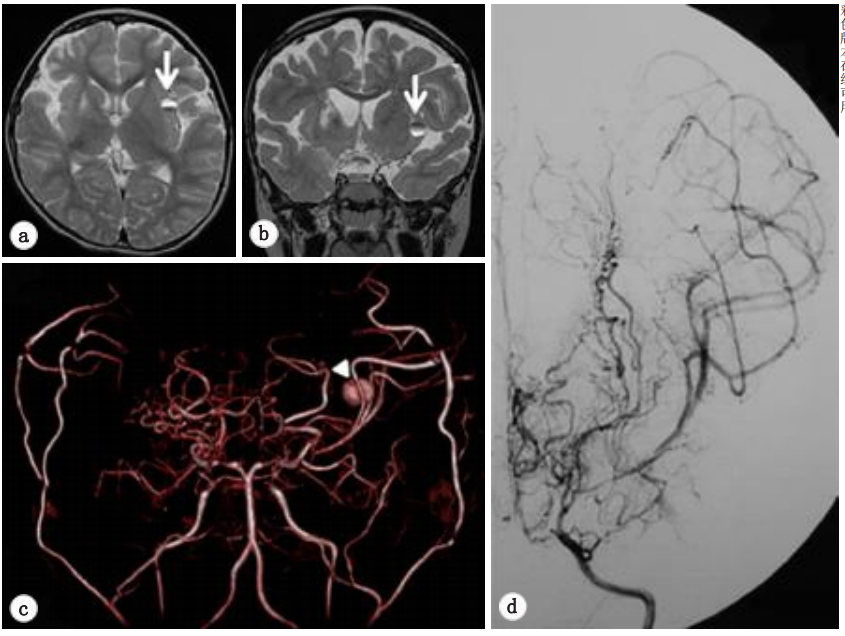

第二次手术的一年半后,在一次常规随访中,MRI发现桃子左侧岛叶有一个小病变(如图4a)。

复查脑MRA显示在左侧MCA远端有一个疑似动脉瘤的圆形病变(图4b),然而,进一步的DSA检查排除了一个动脉瘤可能(图4c )。

图4:轴向(a)和冠状(b)T2加权MRI显示左侧岛叶皮质有一个小的圆形混合强度质量(箭头)。(c)体积渲染磁共振血管造影,在大脑中动脉的左远端(箭头)发现一个浆果状病变,疑似大动脉瘤。(d)数字减影血管造影,左侧颈内动脉造影术未发现动脉瘤等异常表现。